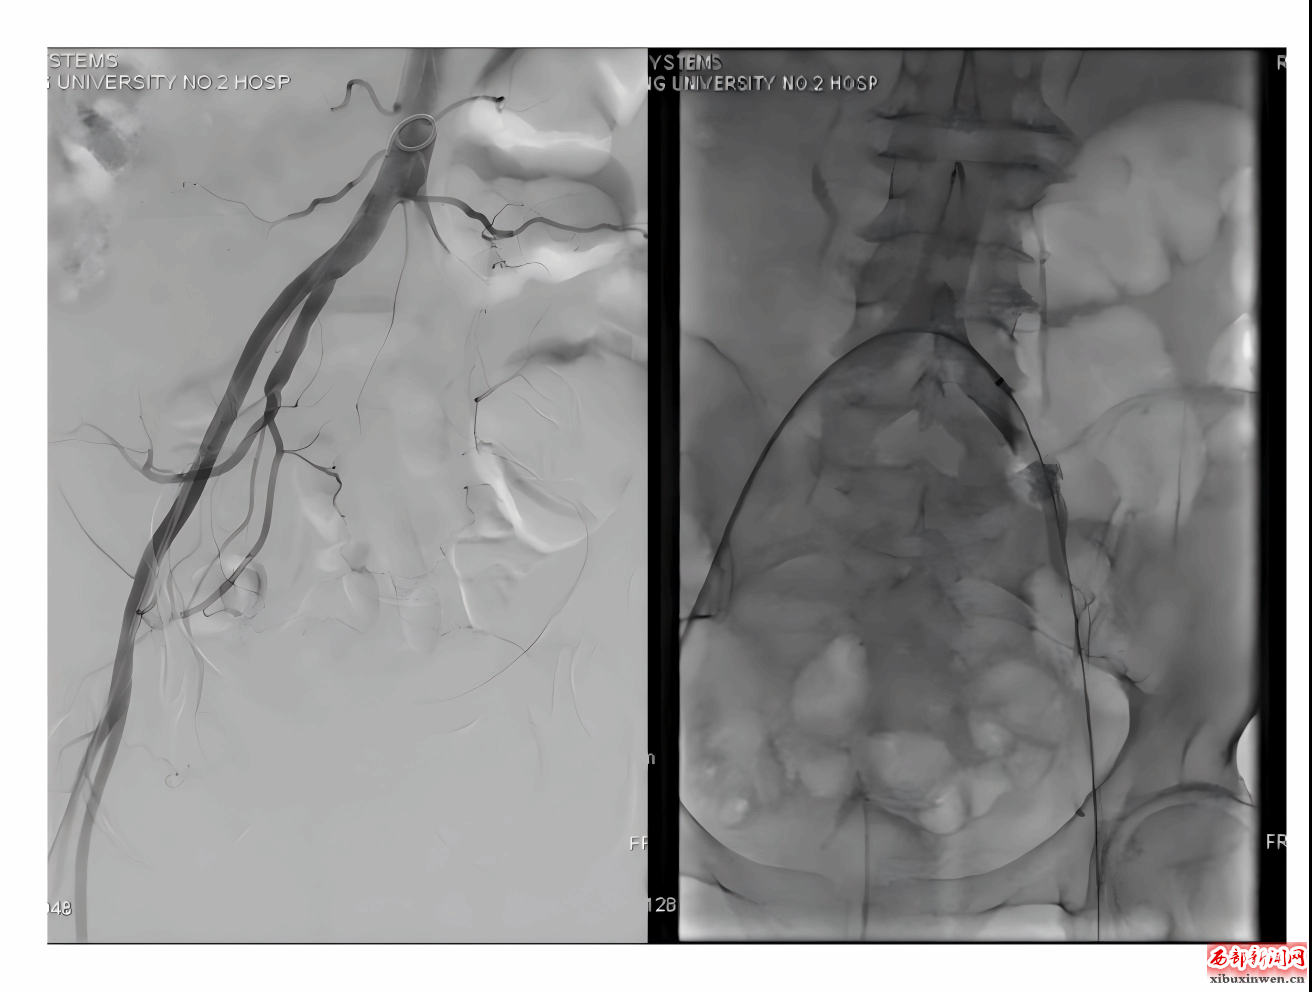

面对如此复杂特殊的病例,血管外科主任马建仓迅速调度专业团队,从多个维度进行多学科评估,最终制定了适合患者的最优救治方案。经过3小时的急诊手术,医生成功开通了患者闭塞的动脉,恢复了下肢的血供。术中造影发现,患者左侧髂动脉、股动脉、腘动脉均充满血栓,医生通过机械抽栓技术和球囊扩张成形术,成功取出了大量血栓,并恢复了患肢的血流供应。